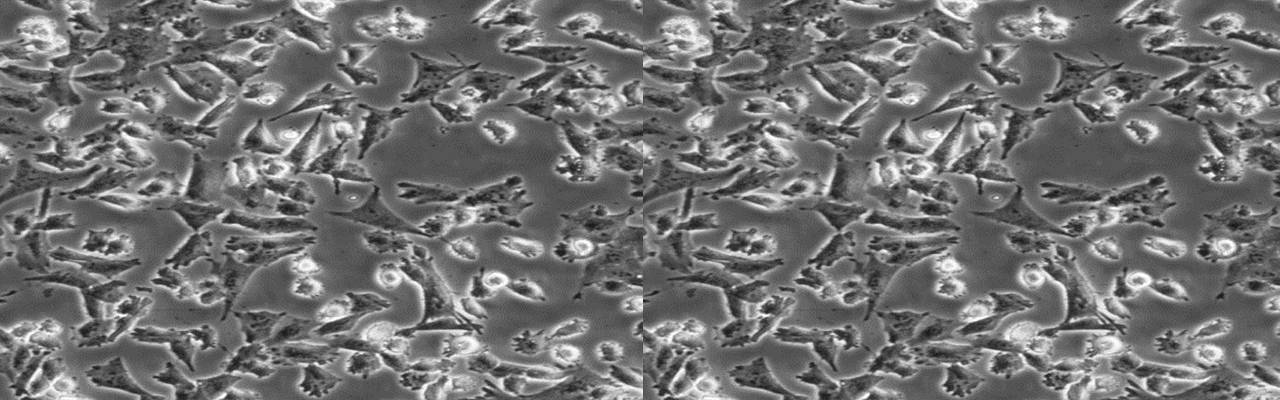

| 细胞全名 | PATU8988T(人胰腺癌细胞) |

| 生长特性: | 贴壁 |

背景资料:建立于1985年,由原发性胰腺腺癌肝转移的64岁妇女;PA-TU-8988S姐妹细胞株